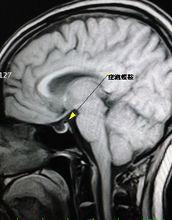

空泡蝶鞍MRI矢狀面(一)鞍隔的先天性解剖變異 Buoch屍檢788例中,發現僅有41.5%鞍隔完整,21.5%鞍隔為2mm寬的環,5.1%鞍隔完全缺如,而在該組中,因鞍隔缺損致原發性空泡蝶鞍的發病率為5.5%。鞍隔不完整或缺如,在搏動性腦脊液壓力持續作用下使蛛網膜下腔疝入鞍內,以致蝶鞍擴大,骨質吸收,脫鈣,垂體受壓萎縮而成扁平狀貼於鞍底。

(三)核磁共振檢查 垂體組織受壓變扁,緊貼於鞍底,鞍內充滿水樣信號之物質,垂體柄居中,鞍底明顯下陷(圖1510)。